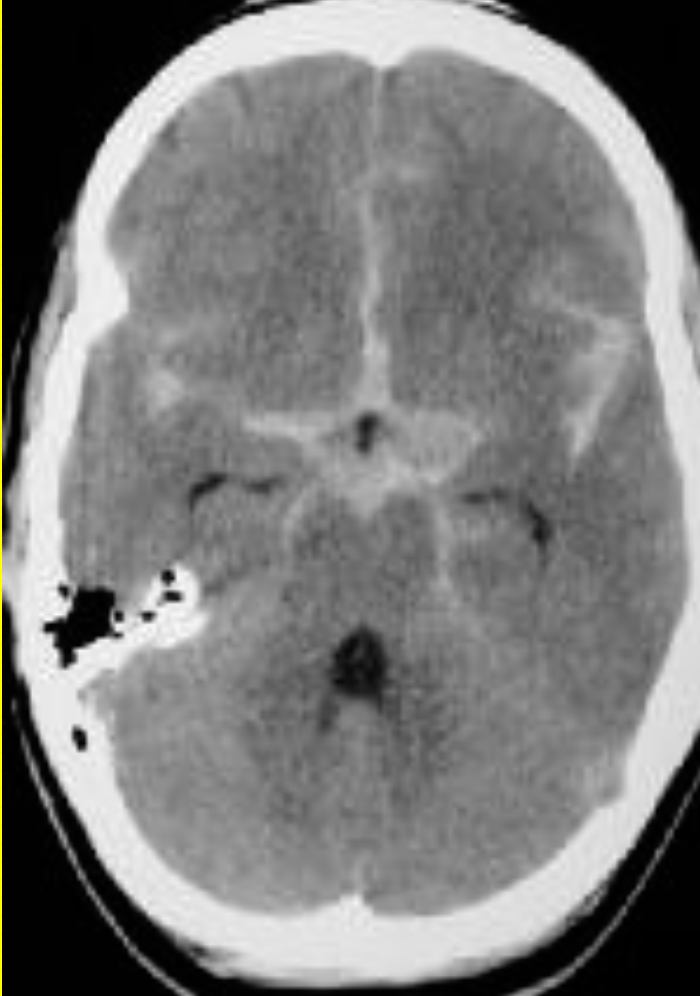

Case 12

A 54-year-old woman presented with a sudden onset thunderclap headache and neck pain for 2 days.

What is the abnormality in the image shown?

a. Blood mixed with CSF filling the subarachnoid space -

What is the likely diagnosis?

a. Subarachnoid hemorrhage -

b. Hyper dinse lesion -

a. Meningitis